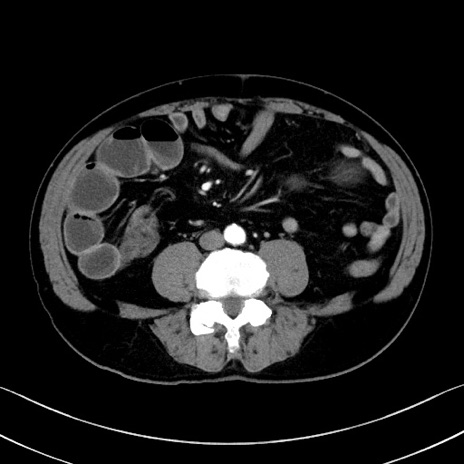

症例35(横断像)

【症例】70歳代 男性

【主訴】腹部膨満、嘔吐

【現病歴】昨日より腹部膨満感出現。本日増悪し、仙痛出現。嘔吐あり、受診。

【既往歴】糖尿病、胆摘後

【身体所見】BP 149/80mmHg、HR 74/min、BT 35.9℃、腹部:膨満、軟、圧痛なし。腸雑音減弱あり。上腹部正中切開瘢痕あり。

【データ】WBC 13500、CRP 1.72